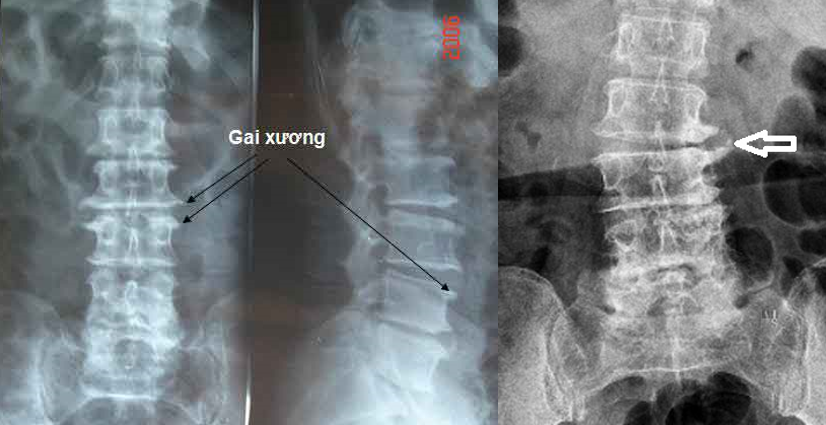

− Xquang thường quy cột sống thẳng, nghiêng: hình ảnh hẹp khe đĩa đệm, mâm đĩa đệm nhẵn, đặc xương dưới sụn, gai xương thân đốt sống, hẹp lỗ liên hợp đốt sống. Trường hợp trượt đốt sống có chỉ định chụp chếch 3/4 phải, trái nhằm phát hiện tình trạng gẫy cuống đốt sống “gẫy cổ chó”.

+ Xquang cột sống thắt lưng thường quy (thẳng – nghiêng – chếch ¾ hai bên): hẹp khe khớp với bờ diện khớp nhẵn, đặc xương dưới sụn, gai xương thân đốt sống, hẹp lỗ liên hợp đốt sống.